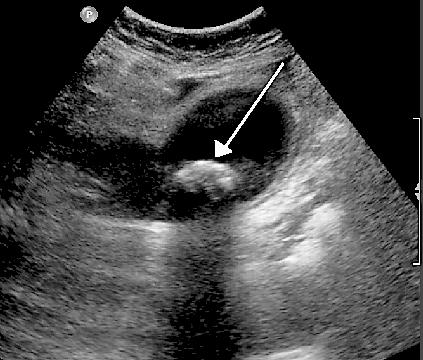

Autre exemple : lorsque les ultrasons traversent la bile dans la vésicule biliaire, ils renvoient un écho puissant s'ils rencontrent un calcul biliaire solide, comme dans l'image échographique ci-dessous. La flèche indique un calcul biliaire dans la vésicule biliaire.

Image échographique des calculs biliaires

Par James Heilman (Travail personnel), via Wikimedia Commons